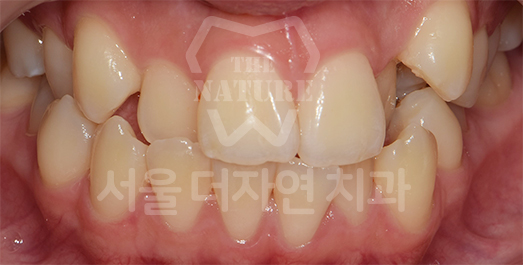

Diastema (Spacing) Solution

We first diagnose whether the spacing is generalized throughout the dentition or localized to specific areas such as the anterior teeth. Treatment involves attaching orthodontic appliances and

moving the teeth into the vacant spaces to achieve proper alignment.

• BEFORE: 2020.11.12

• AFTER: 2023.04.06